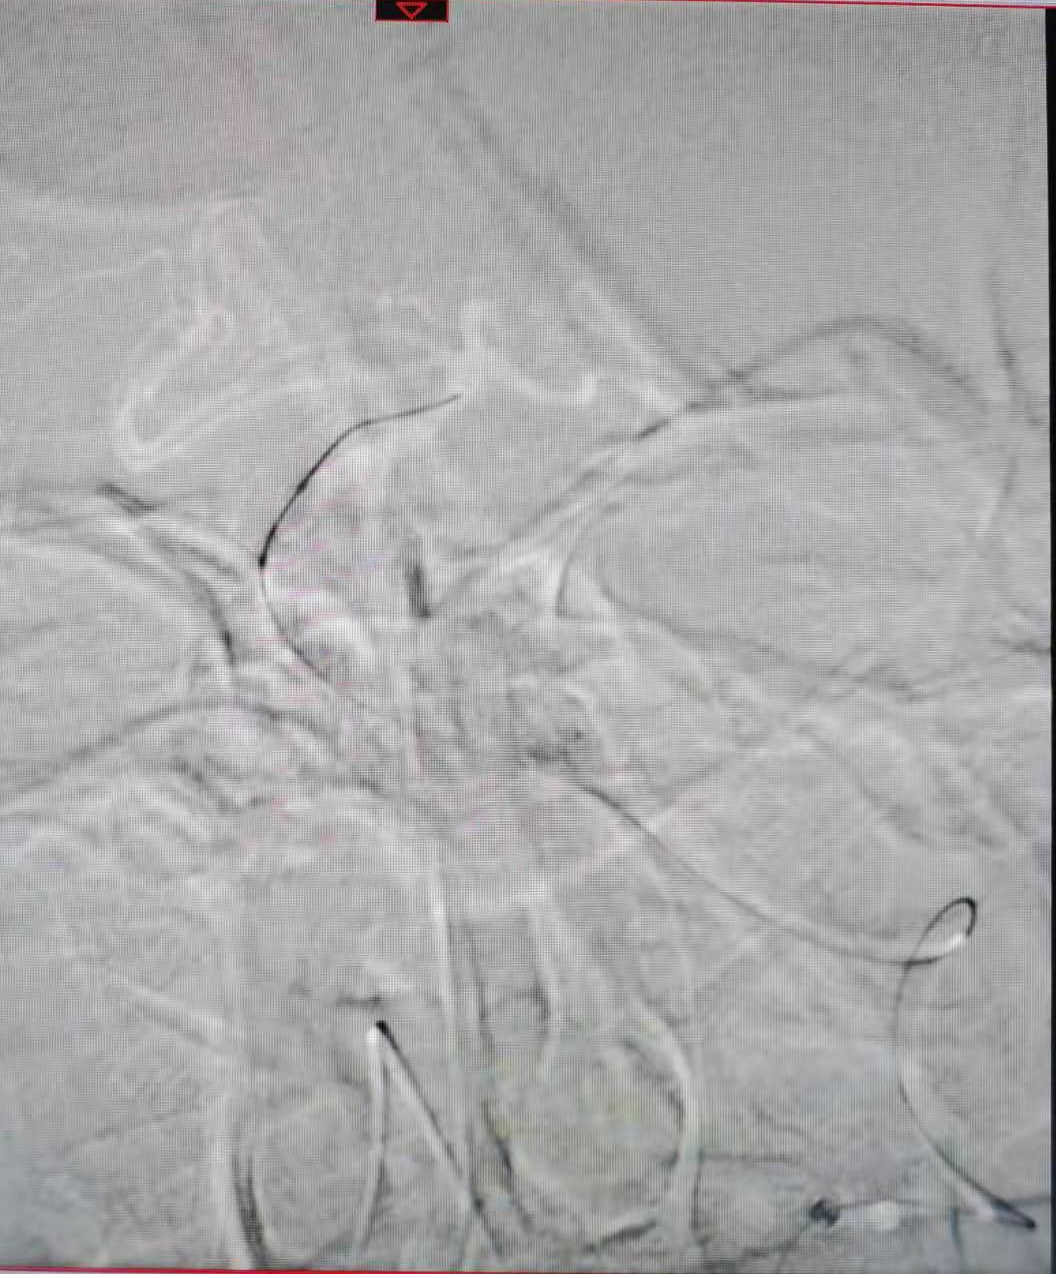

通过长交换技术保留transend微导丝,将加奇SacSpeed® 2.5mm×9mm颅内球囊,放置在基底动脉闭塞部位。

8atm压力扩张闭塞部位。

同样方法给予9atm压力再次扩张闭塞部位。

通过长交换技术,将XT-27定位在右侧大脑后动脉P2段,将Neuroform颅内支架3.5×15mm,定位在基底动脉狭窄处。

释放支架。